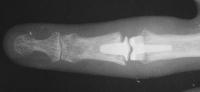

This gentleman presented with stiffness and lateral deviation of the ring finger proximal interphalangeal joint following volar plate arthroplasty for dorsal fracture dislocation.

Preoperative and postoperative radiographs.